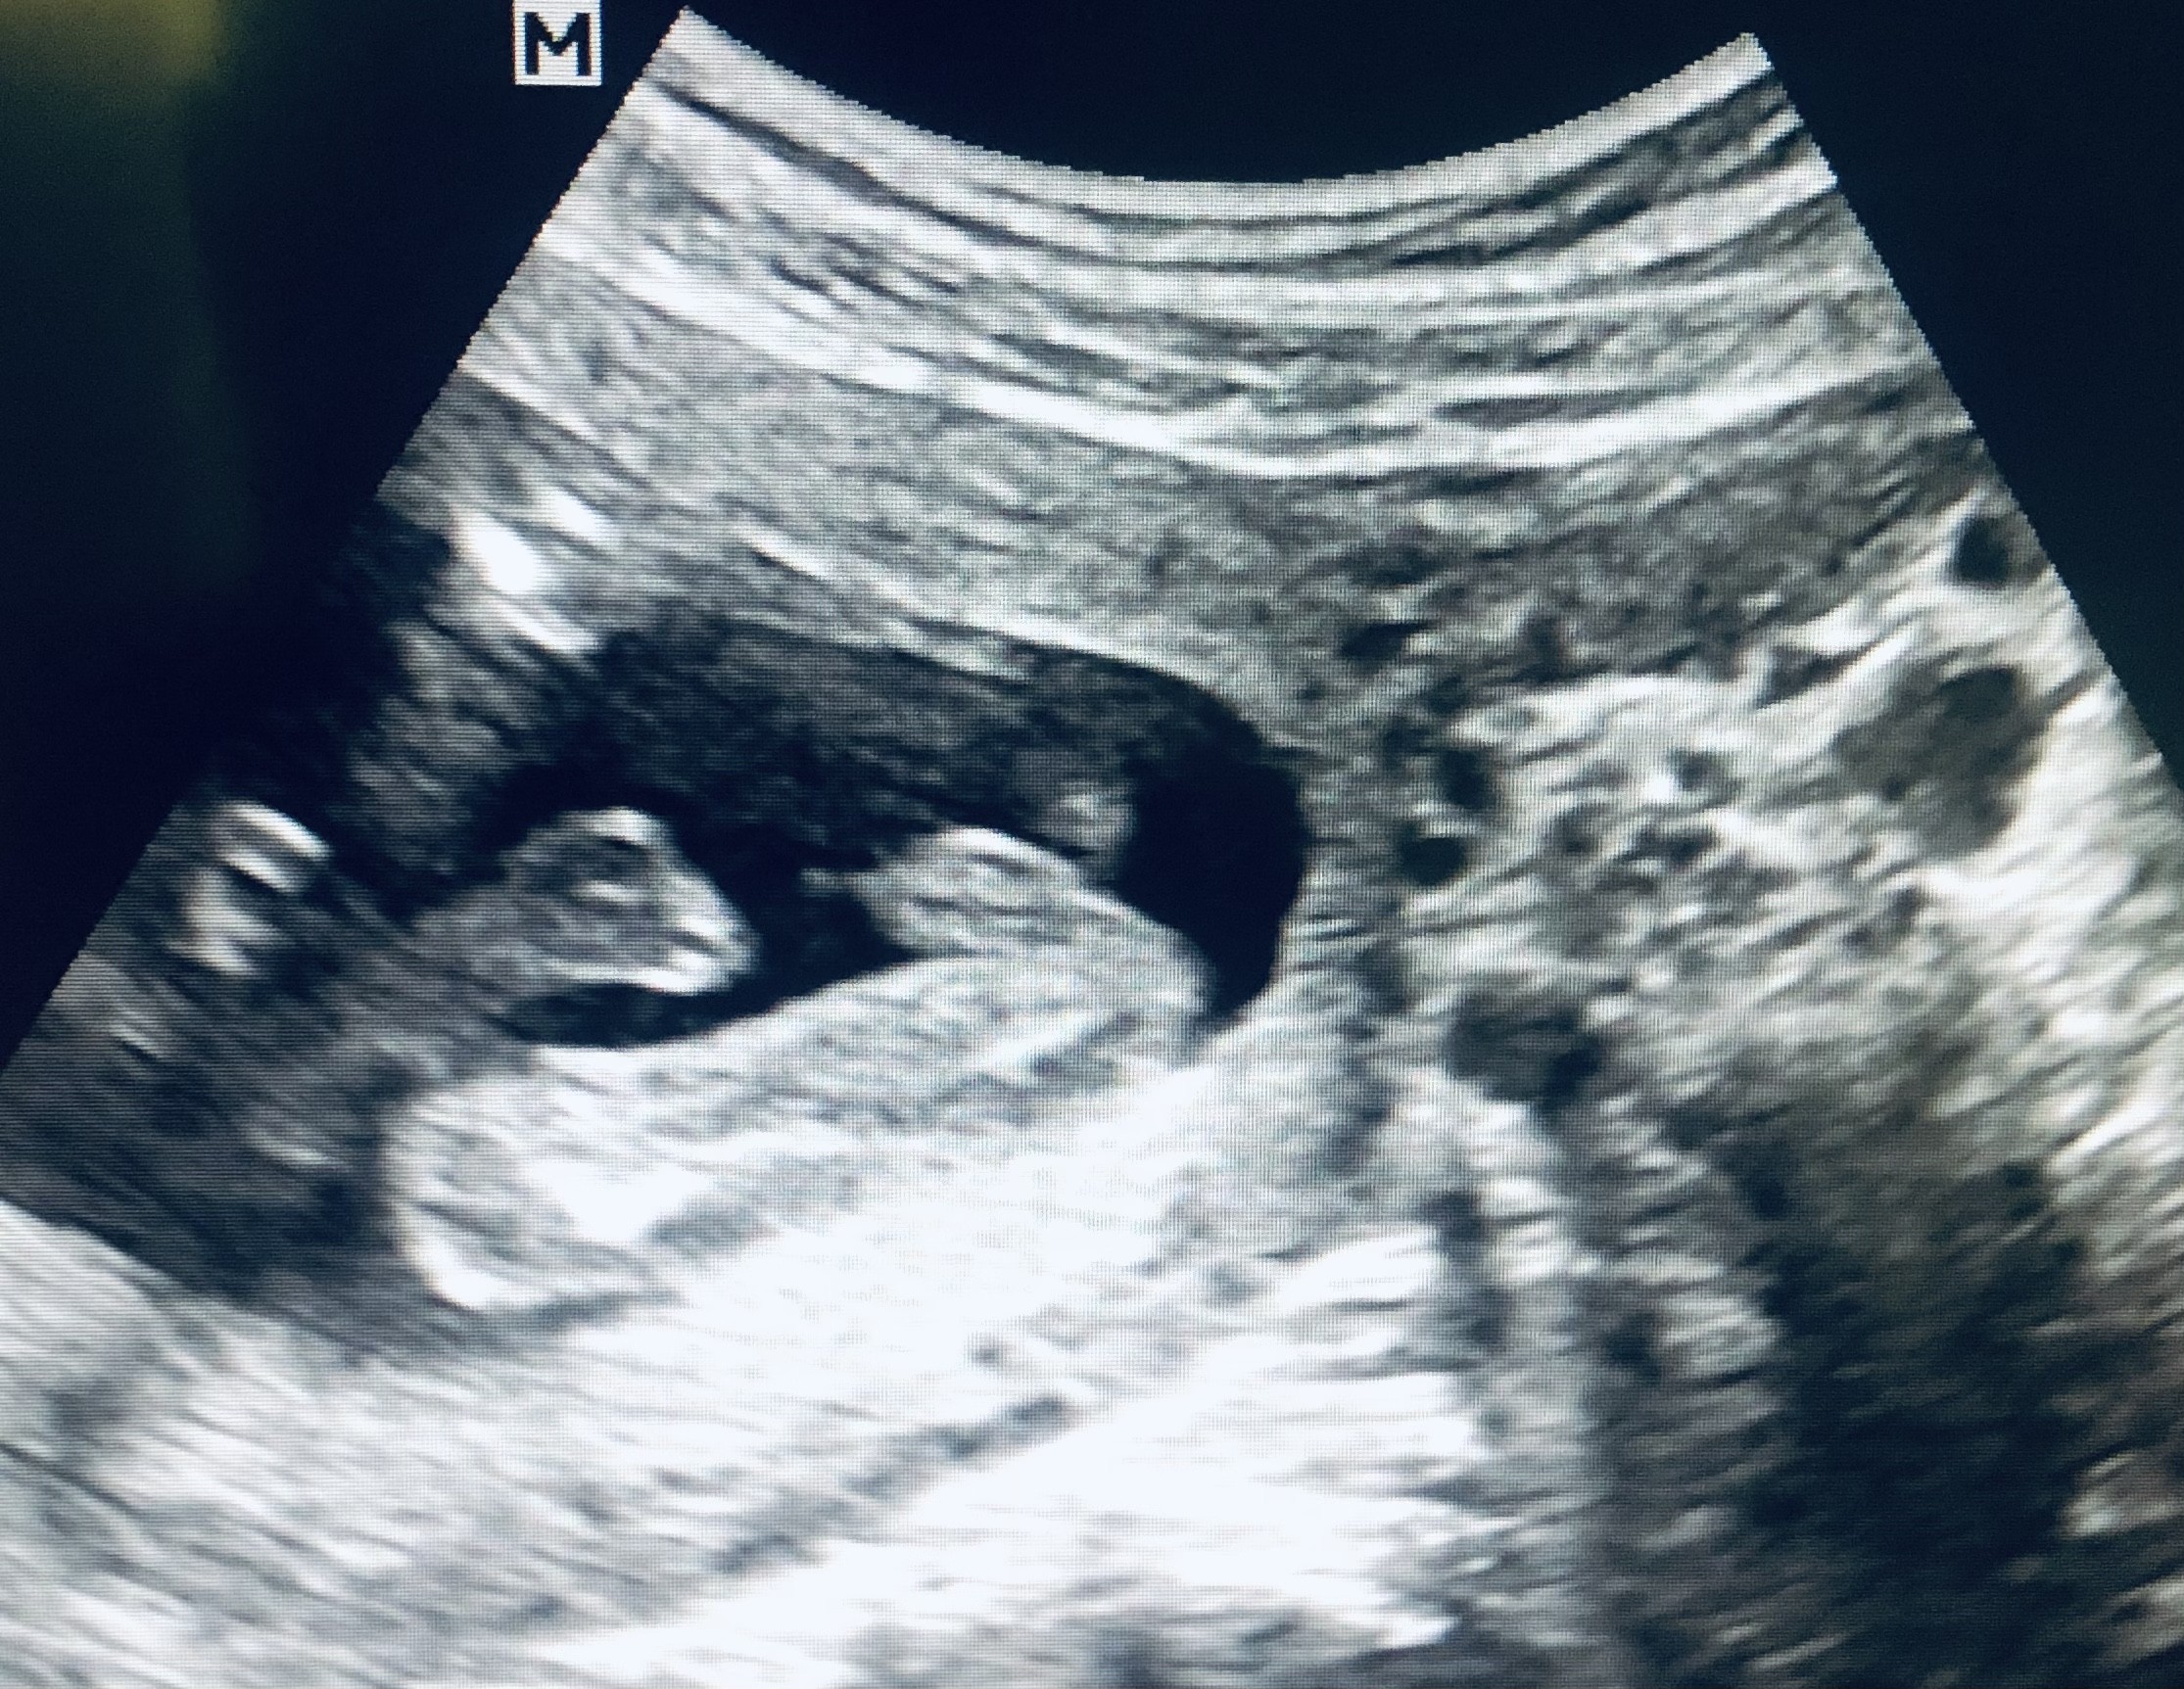

Witam w 19 tygodniu ciąży dowiedziałam się ze będę miała dziewczynkę w 20 tyg okazało się jednak , że to chłopak. Sama już nie wiem bo na jednym usg widać na pewno dziewuche a na drugim chłopca. Może to pempowina ?? Może ktoś mi pomoże rozwiązać ta zagadkę

Dziewczyny a u mnie widać czy to wargi u dziewczynki czy siusiak? Bo mi to bardziej wyglada na wargi sromowe niż siusiaka bo nie widzę znowu jajek 😂